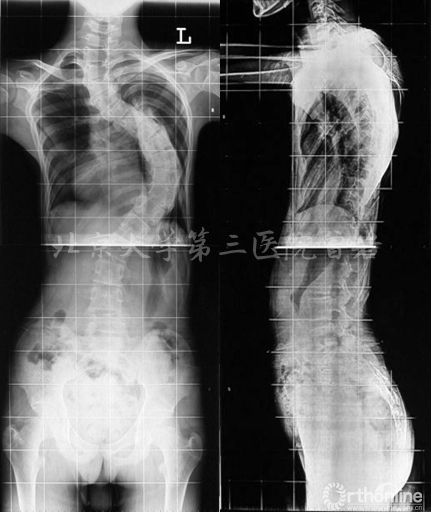

术前X线(图5):侧凸上胸弯Cobb 52°,下胸弯Cobb 52°,胸腰弯Cobb 65°,后凸角度102°,左肩高于右肩。

图5